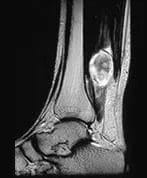

Posterior Tibial Neuroma

A patient presents with swelling in the right calf above the ankle.

Findings

The sagittal MR images demonstrate a well-defined lobulated mass in the posterior compartment of the right calf. The lesion enhances after contrast and the features are suggestive of a posterior tibial neuroma.